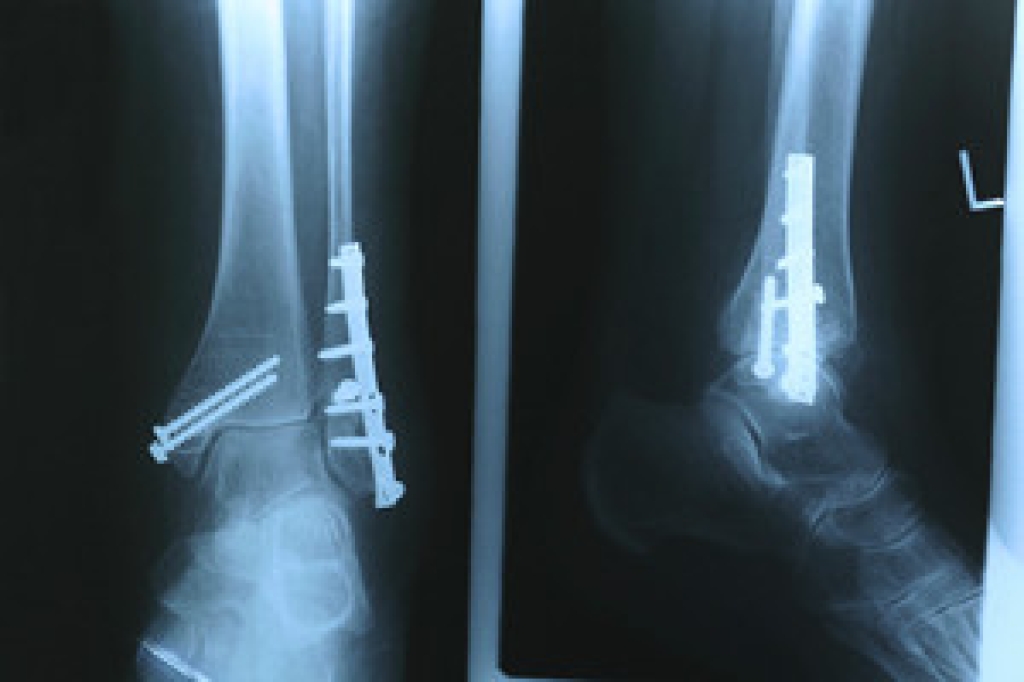

Dealing with Stress Fractures of the Foot and Ankle

Stress fractures occur in the foot and ankle when muscles in these areas weaken from too much or too little use. The feet and ankles then lose support when walking or running from the impact of the ground. Since there is no protection, the bones receive the full impact of each step. Stress on the feet can cause cracks to form in the bones, thus creating stress fractures.